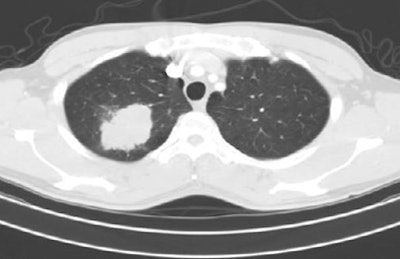

![]() |

| A lung nodule unmarked (top) and marked (bottom) from the LIDC database. All images courtesy of the National Cancer Institute. |